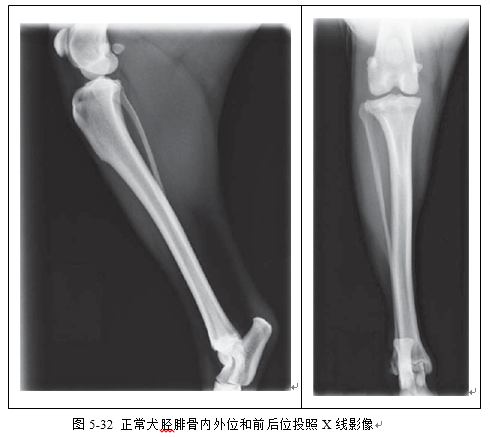

(3)识别胫腓骨、股骨、跗关节、膝关节X线影像(图5-32、5-33、5-34、5-35)。